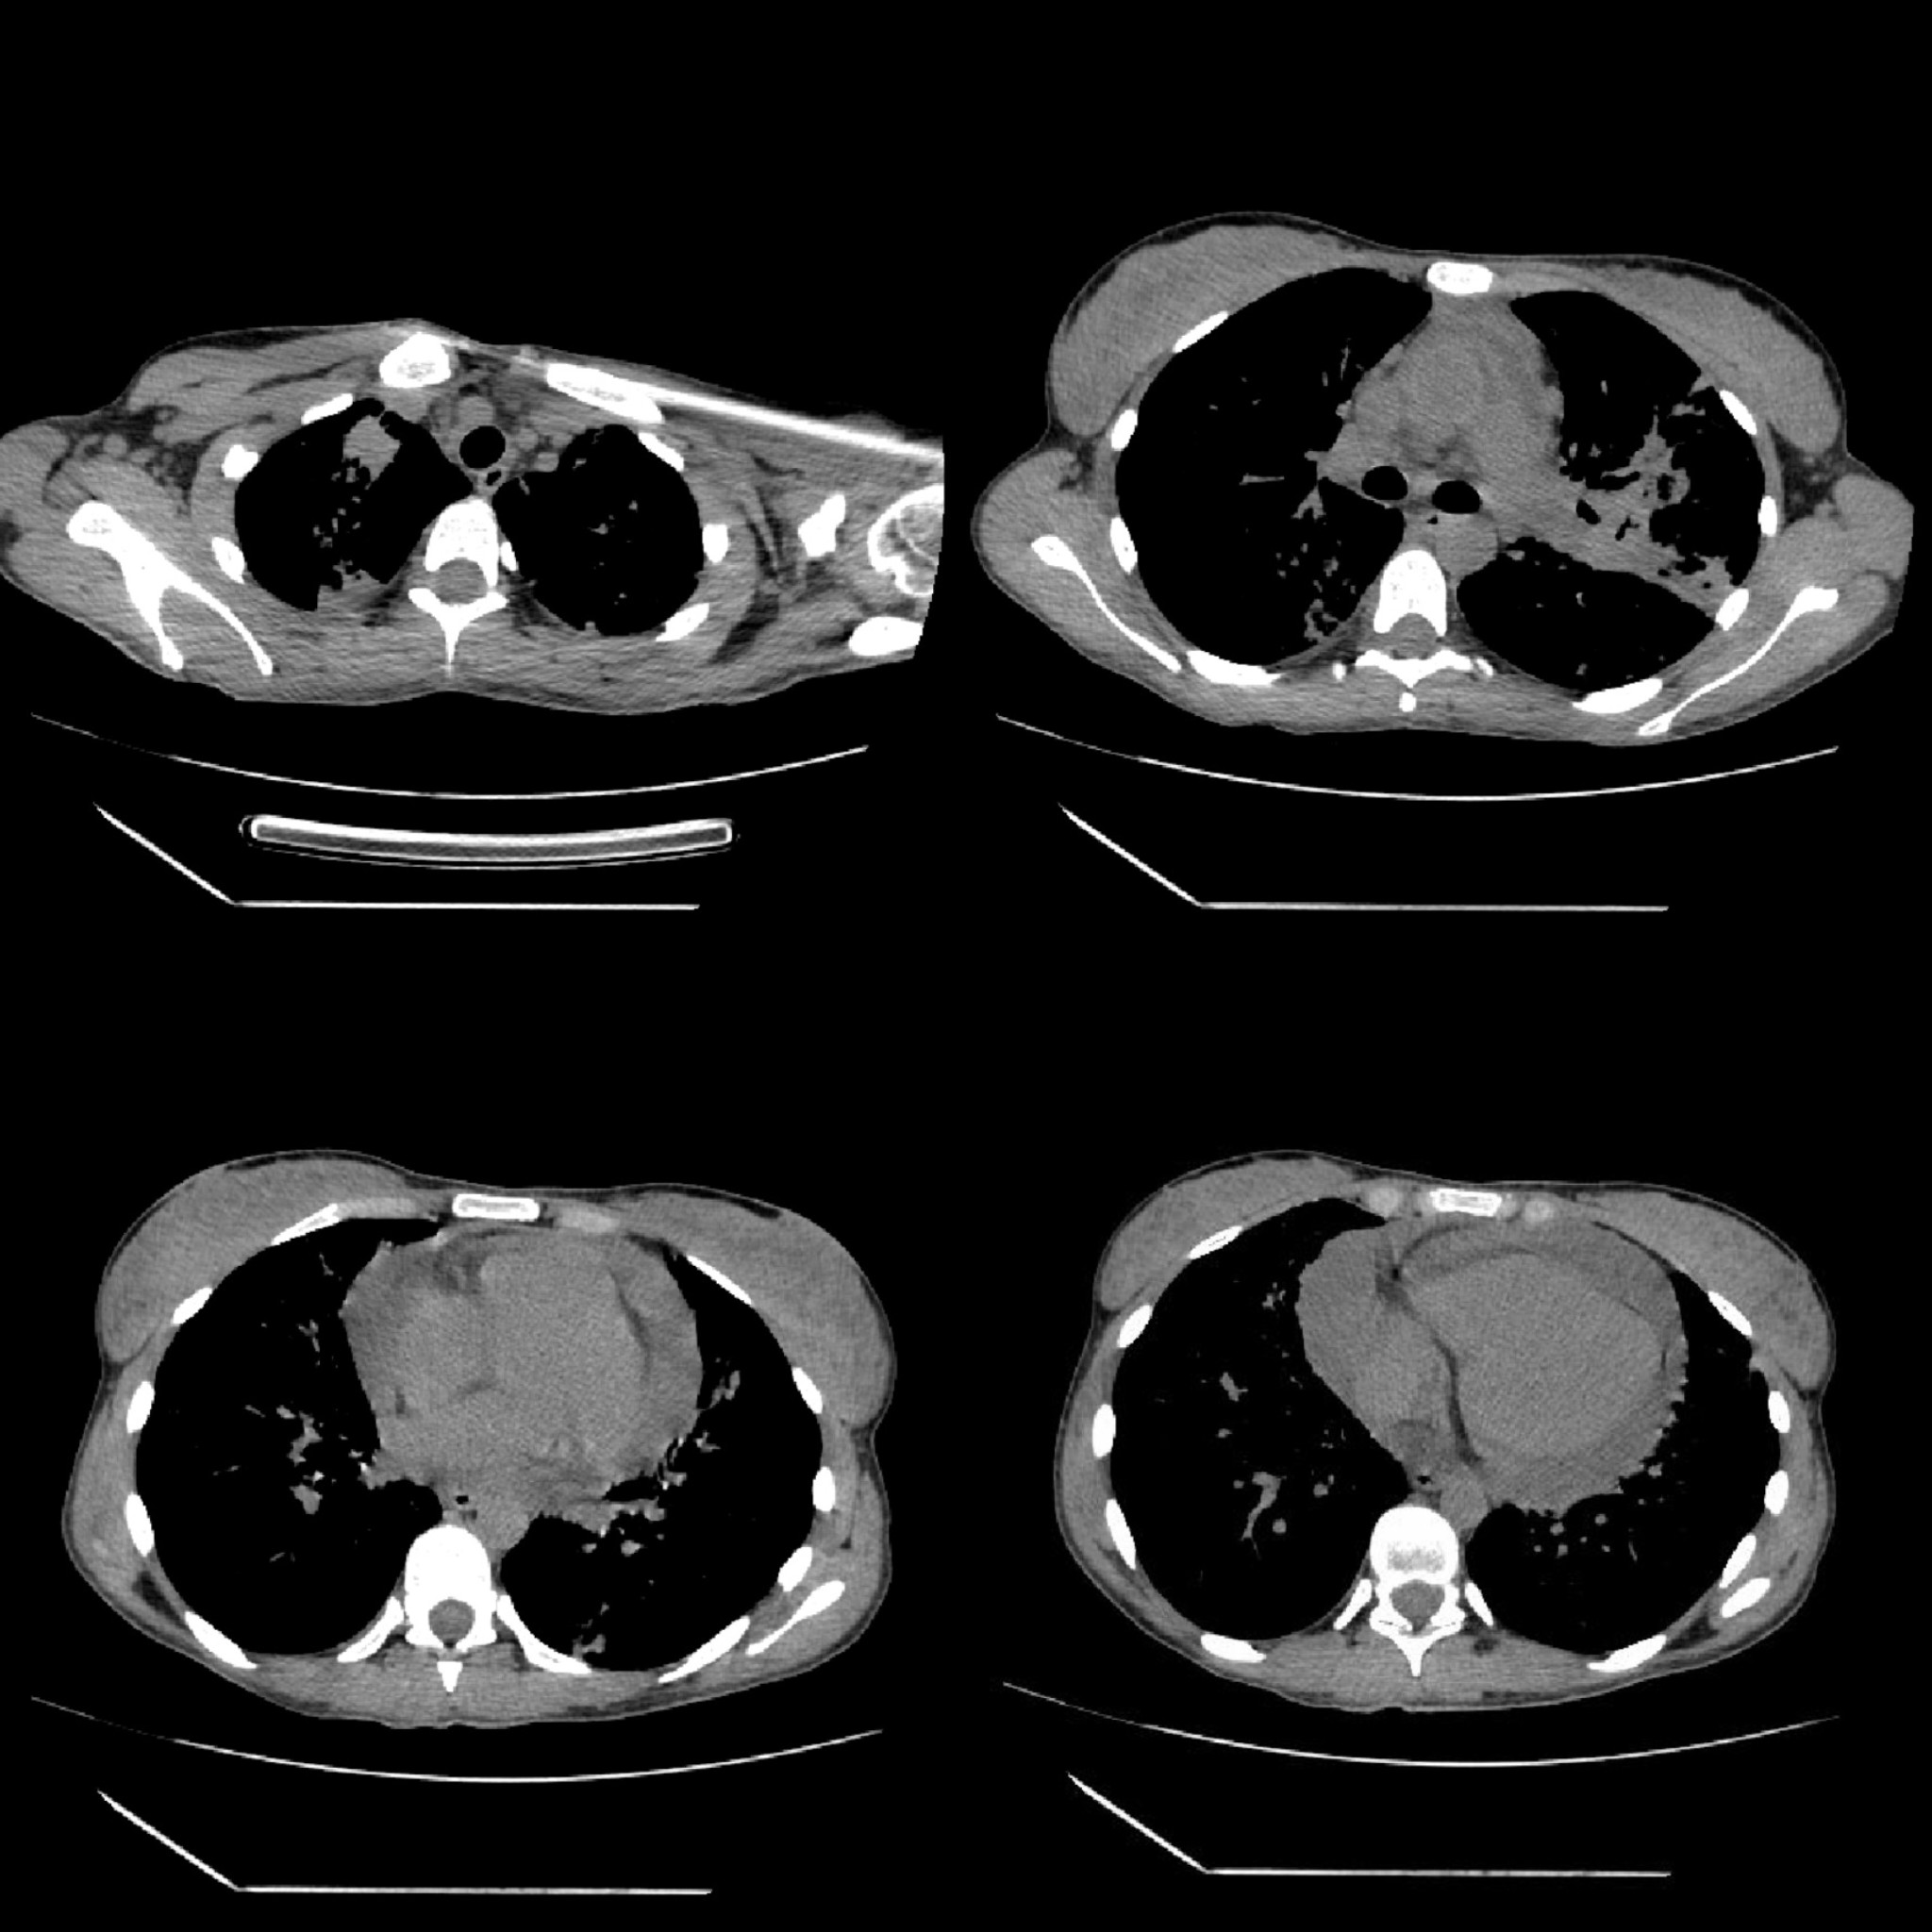

Non-contrast chest CT demonstrated diffuse miliary nodularity with focal consolidations in the right upper lobe segment S1 and left upper lobe segment S1, accompanied by hilar and mediastinal lymphadenopathy and a large pericardial effusion measuring up to 4 cm in thickness (Figures 2 and 3). A cardiology consultation was obtained. Screening transthoracic echocardiography (TTE) demonstrated a pericardial effusion measuring 3.8 cm, with evidence of cardiac tamponade. Although the patient remained hemodynamically stable, the large pericardial effusion with echocardiographic tamponade physiology warranted urgent echocardiography-guided pericardiocentesis to prevent progression to obstructive shock. The procedure reduced the effusion to 2.0 cm with resolution of tamponade, and a pericardial drain was left in situ. Pericardial fluid, sputum, urine, and stool samples were collected and tested for Mycobacterium tuberculosis (MTB) using smear microscopy, the Xpert MTB/RIF assay, and culture. MTB was detected by the Xpert MTB/RIF assay (positive for MTB DNA without rifampicin resistance) in multiple specimens, including sputum, pericardial fluid, and feces. Smear microscopy was negative in all samples except for scant acid-fast bacilli (AFB) detected in a single sputum specimen (Table 1).